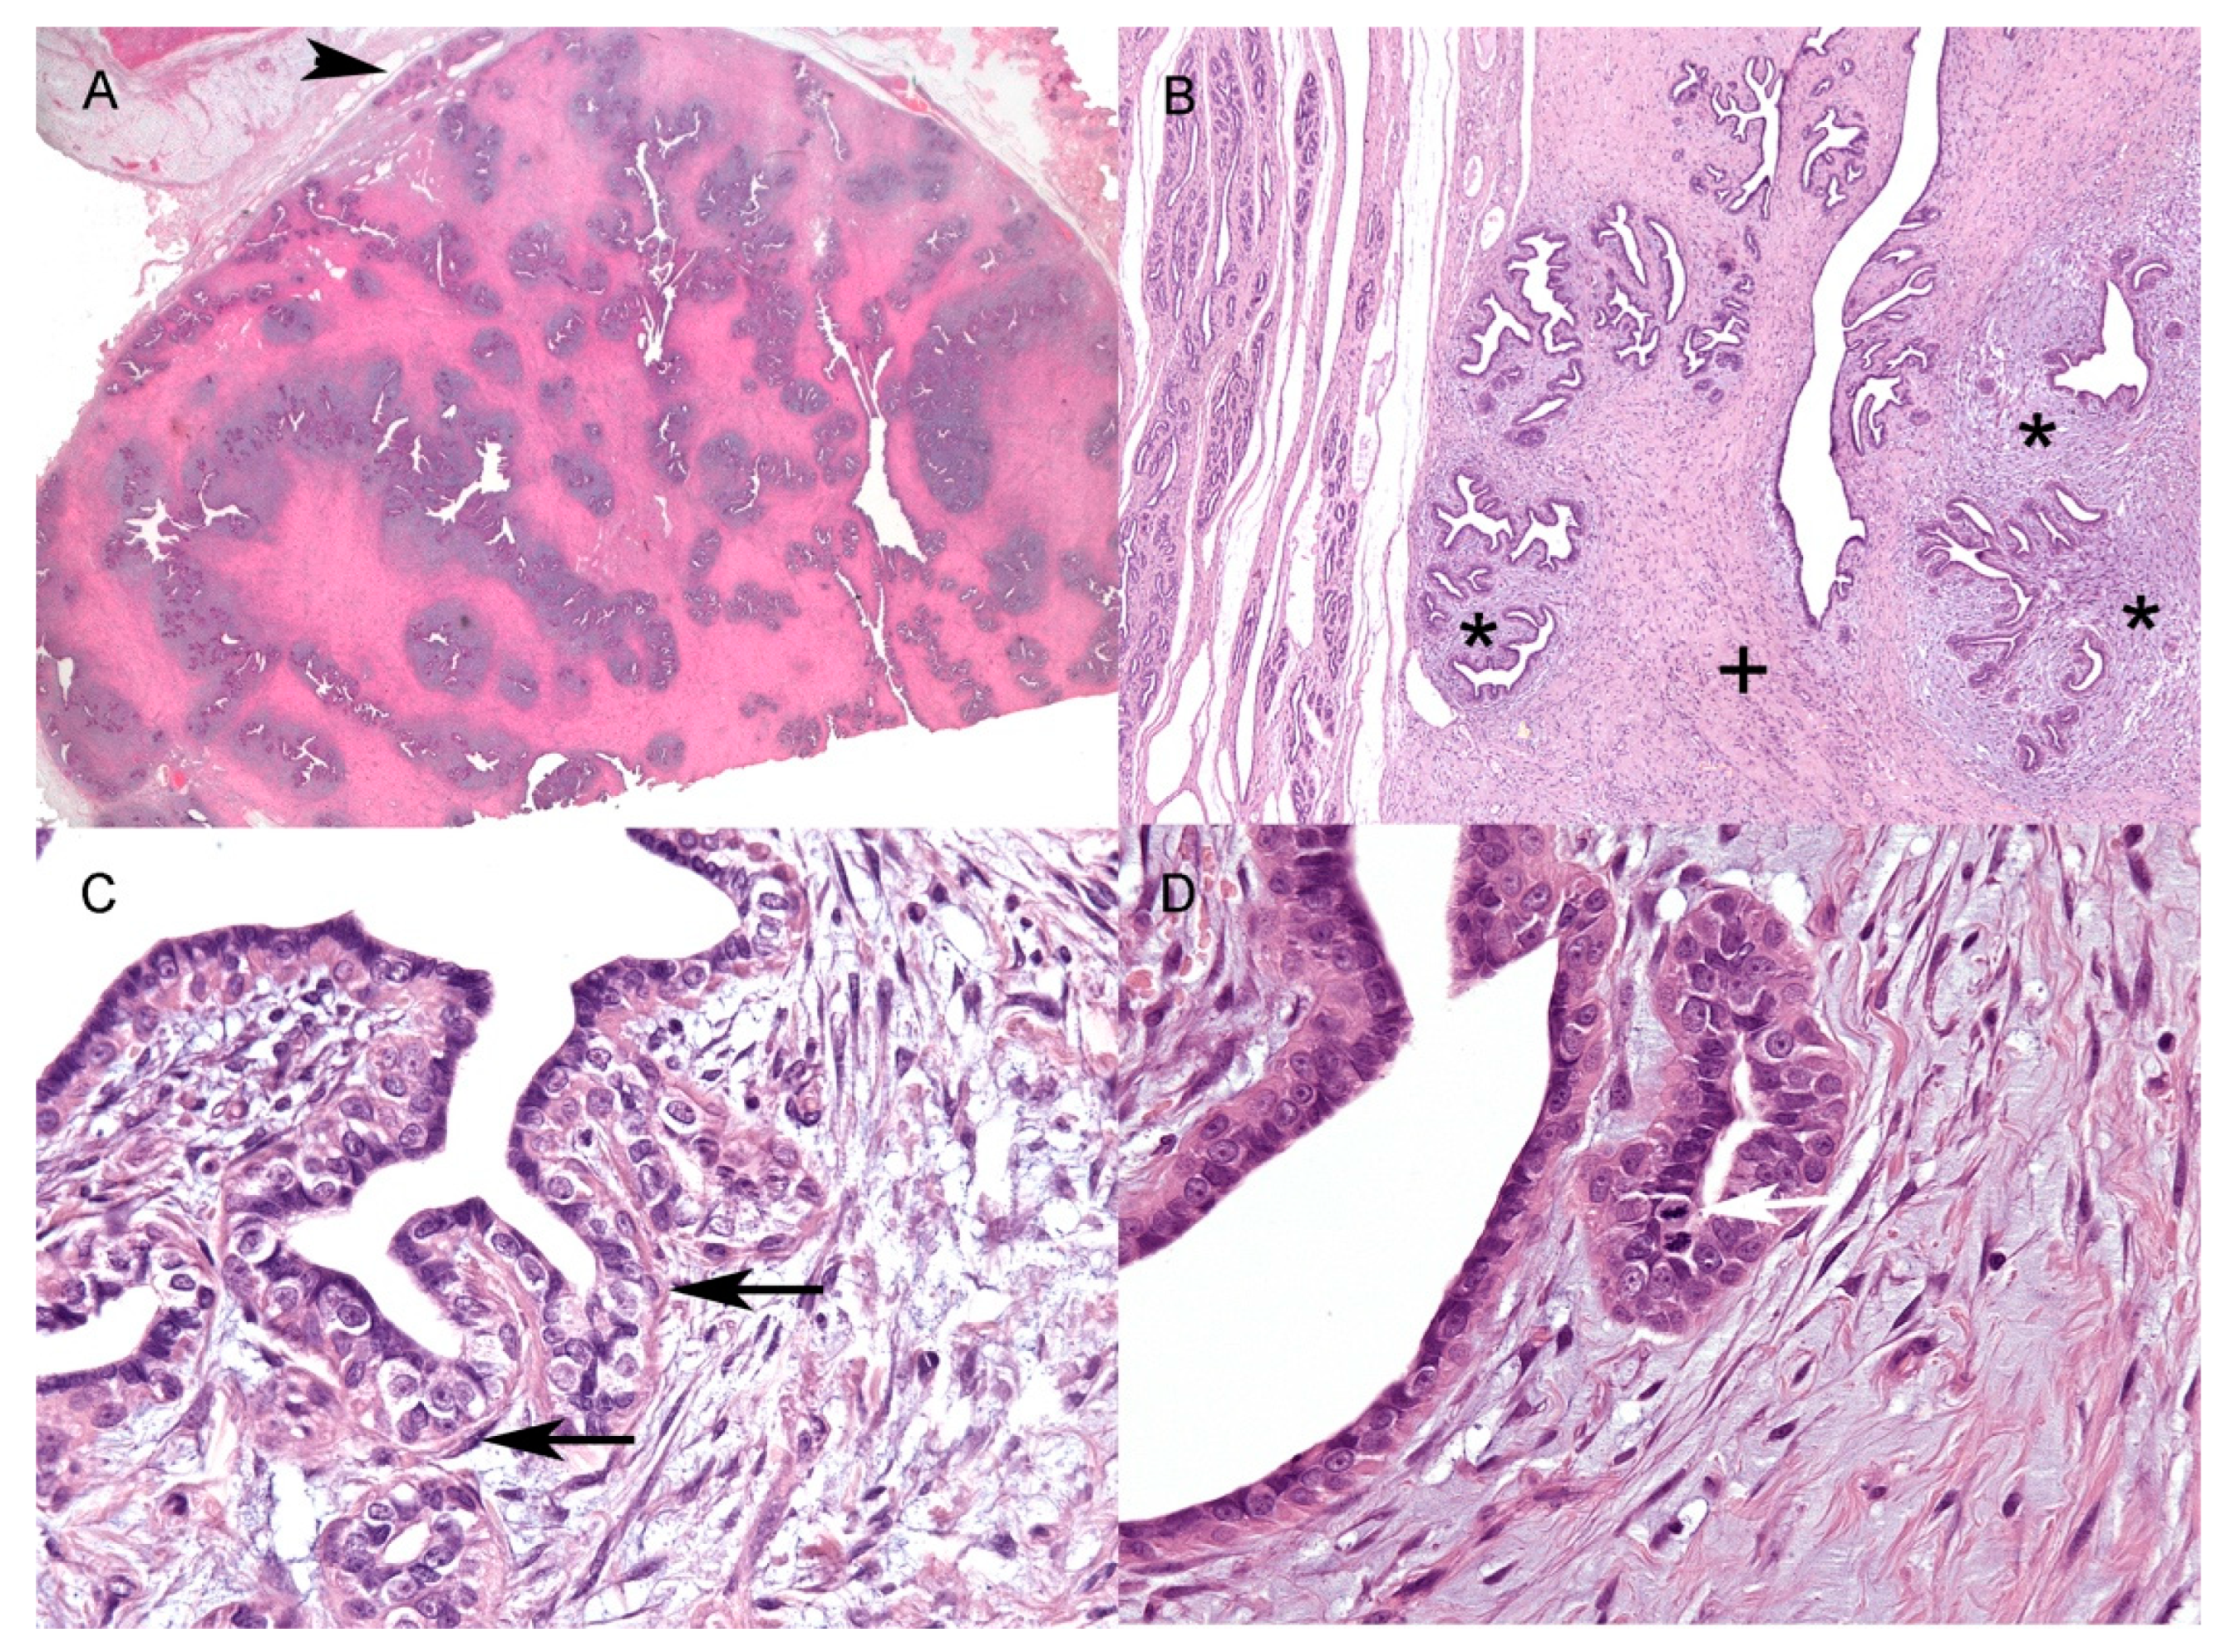

All of the samples were characterised by single, moderately to densely cellular well-demarcated expansile nodules (Figure 1A) with a maximum size of 4.3 × 2.1 cm and a minimum size of 1.4 × 0.7 cm (Table 2).

Histopathological features of feline mammary fibroadenoma. (A) Well-defined subcutaneous fibroadenoma with adjacent unaffected mammary gland (arrowhead) (size of the nodule at histology: 4.3 × 2.1 cm) (HE, 2×); (B) Unaffected mammary gland (on the left) and the lesion showing an elongated duct (centre of the lesion) and lobular-like structures. A more densely cellular, myxomatous intralobular stroma (asterisks) and a more collagenous, poorly cellular interlobular (+) stroma are evident (HE, 4×); (C) Elongated basally located cells (arrows), compatible with myoepithelial cells surrounding the irregularly polygonal epithelial cells (HE, 40×); (D) Frequent mitoses are present mainly within the neoplastic epithelial population (white arrow) (HE, 40×). HE = haematoxylin and eosin.

Depending on the sample, the epithelial component represented from 20 to 80% of the nodules. Neoplastic epithelial cells were arranged in elongated ducts arborizing in lobular-like units of small ducts and tubules (Figure 1B). Multifocally, three of the nine samples showed large ectatic ducts often filled with amorphous, slightly eosinophilic material, sloughed epithelial cells, and foamy macrophages. The epithelial lining of ducts and tubules was composed of one to a maximum of three layers of irregularly polygonal cells, often surrounded by elongated basally located elements, mainly consistent with myoepithelial cells (Figure 1C) (see IHC results). Neoplastic epithelial cells were irregularly polygonal, up to 15 μm in maximum diameter, with mostly indistinct cell borders and a moderate amount of pale eosinophilic homogeneous cytoplasm (Figure 1C,D). The nuclei were round to oval, with coarse to finely stippled chromatin, and one or two prominent central nucleoli (Figure 1C,D). Anisocytosis and anisokaryosis were mild to moderate, with occasional macronuclei. The stromal component was divided into interlobular and intralobular stroma (Figure 1B) [4]. The interlobular stroma, between neoplastic lobular-like units, was consistently composed of thick and dense collagen bundles admixed with rare elongated cells with scant eosinophilic cytoplasm and spindle-to-cigar-shaped nuclei up to three to four microns in size. The interlobular stroma also showed disseminated small-calibre capillaries, mild multifocal oedema, and rare scattered inflammatory cells, mainly macrophages, lymphocytes, plasma cells, and mast cells. The intralobular stroma was closer to small ducts and tubules within and immediately around the lobular-like units (Figure 1B). It was composed of numerous spindle to stellate cells arranged in whorls and short bundles, and embedded in a moderately loose myxomatous matrix (Figure 1B). These cells often had scant cytoplasm and oval to elongated nuclei; occasionally, larger cells with more abundant cytoplasm and plump ovoidal to angular nuclei, up to 10 μm in diameter, were seen. In the stromal component, anisocytosis and anisokaryosis were overall mild, but more evident within the intralobular stroma.

Within the samples, the mitotic count in neoplastic epithelial cells (Figure 1D) ranged from 0 to 8 (mean 3.4 SD ± 2.78; median 3), while, in the stroma (interlobular and intralobular), the mitotic count ranged from 0 to 3 (mean 0.8 SD ± 1.05; median 1) (Table 2).